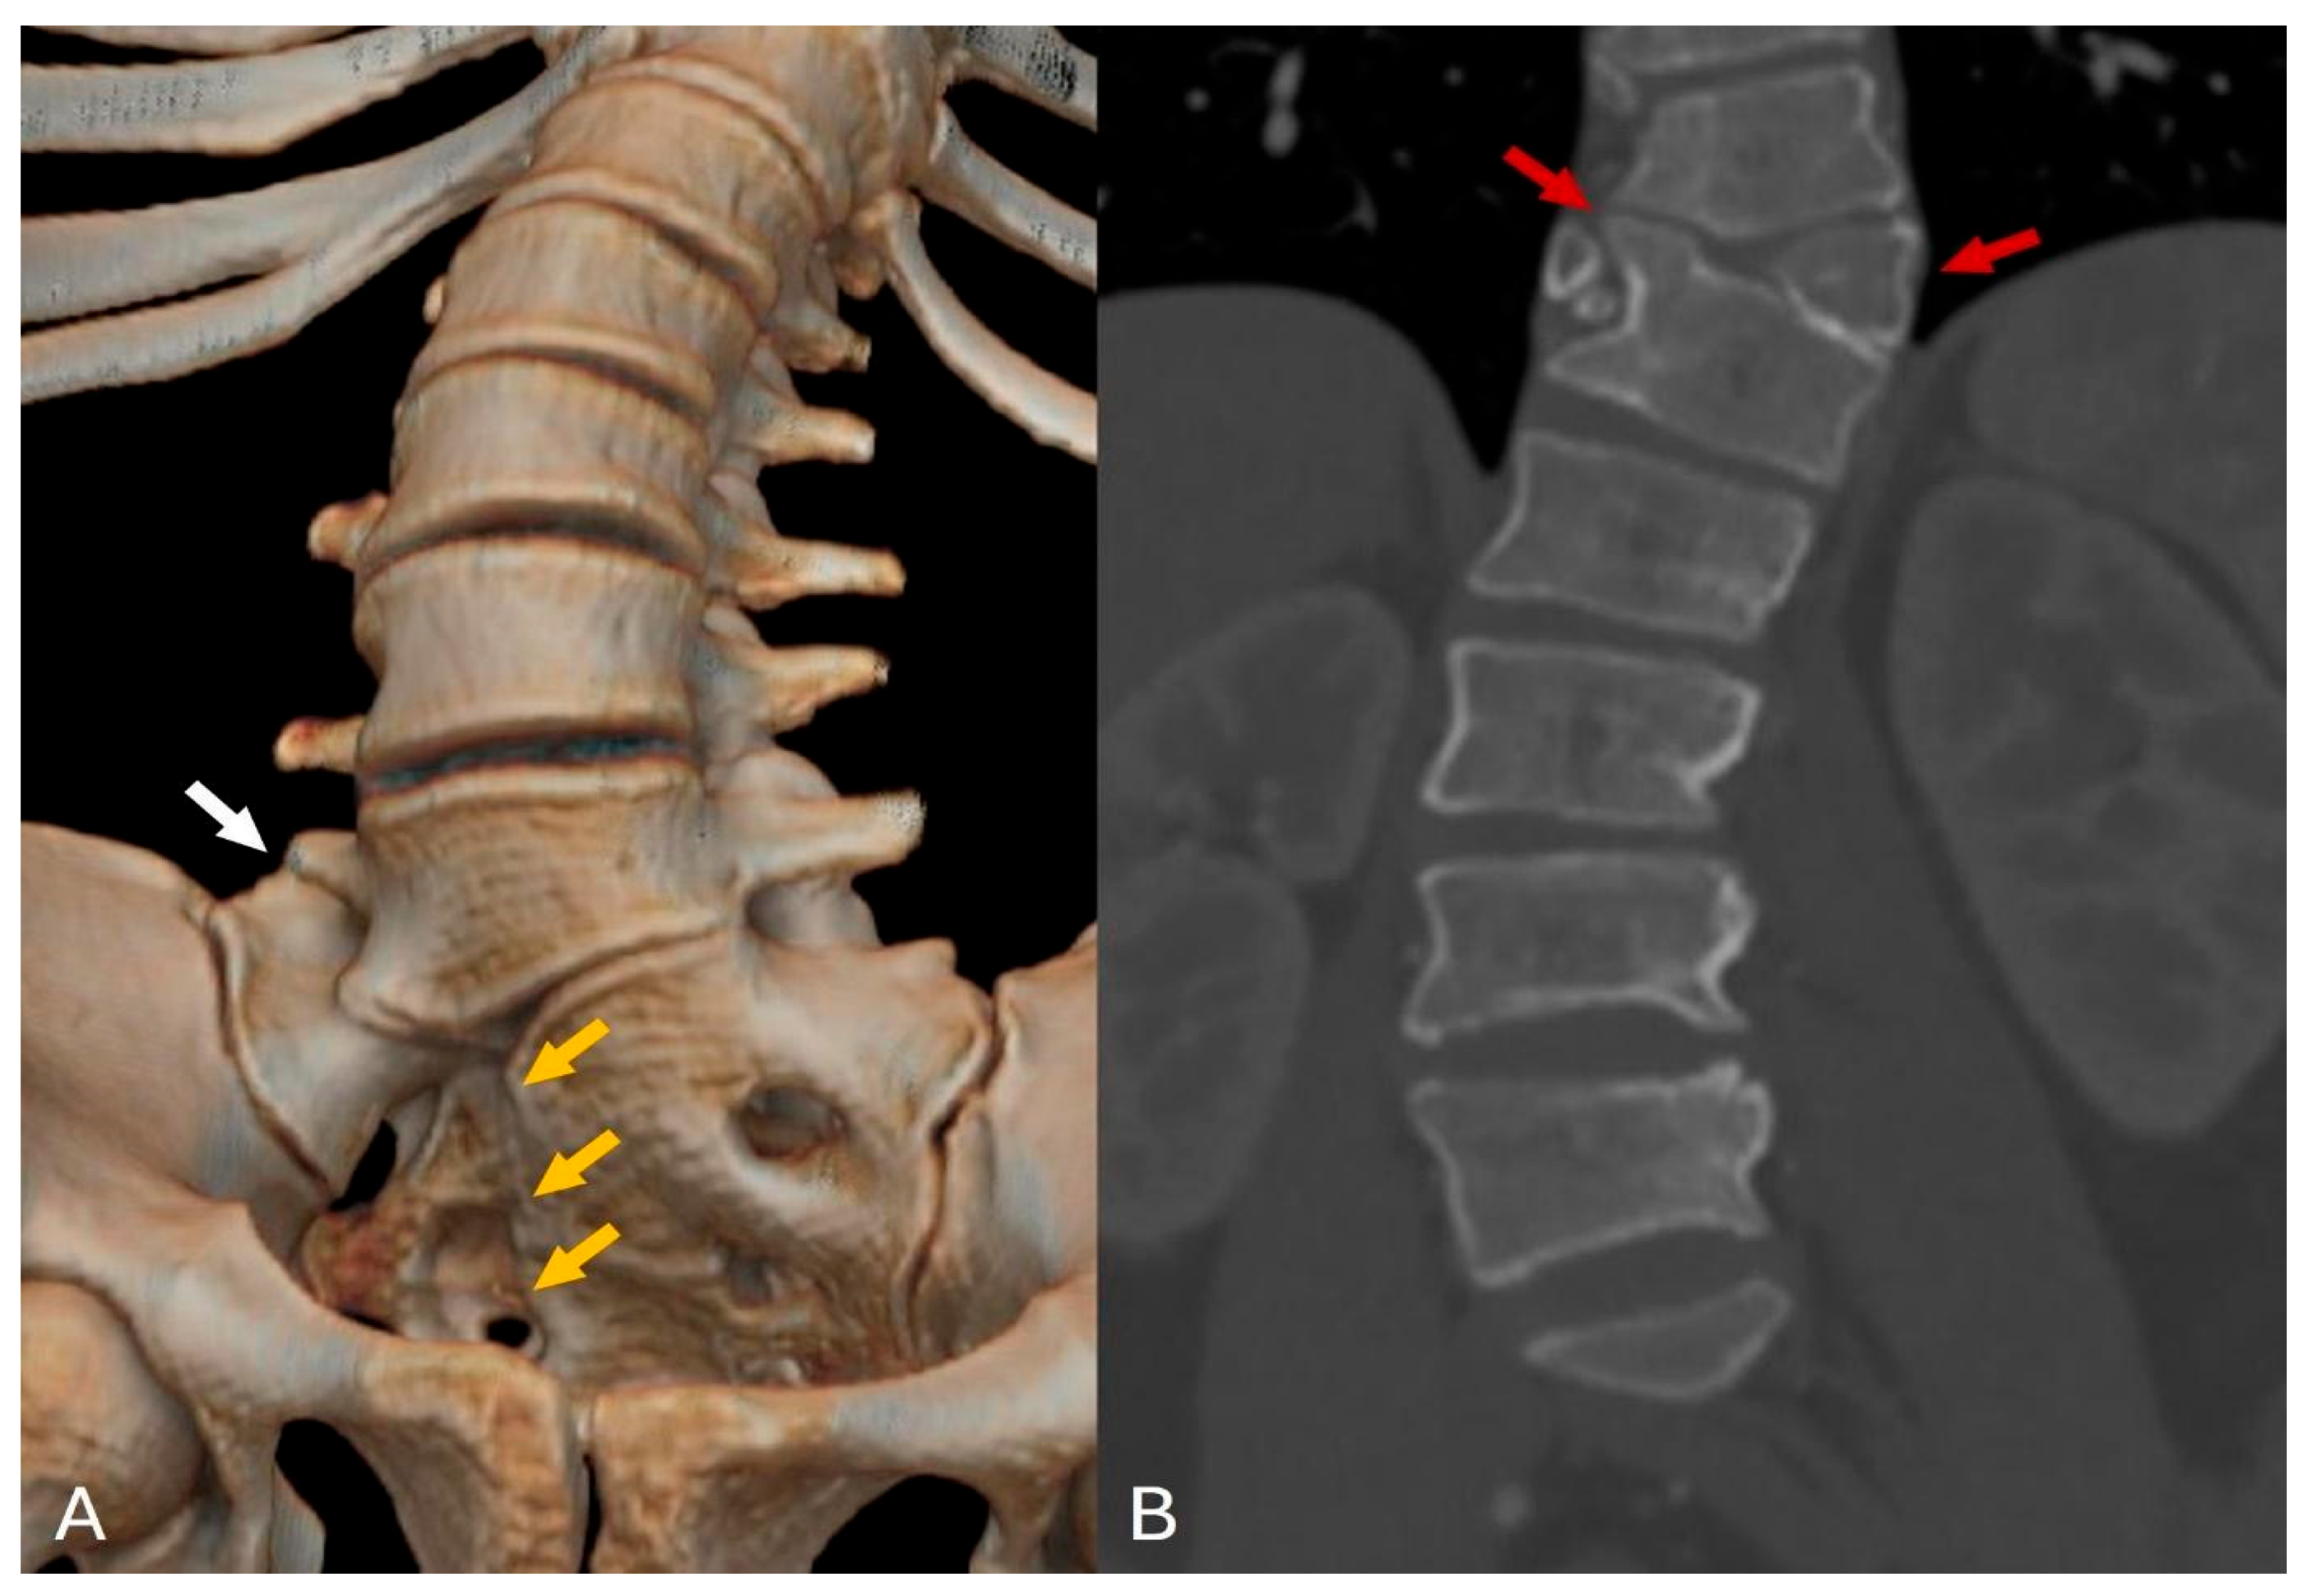

Figure 2.

CT reconstruction and coronal CT imaging: (A) The 3D CT reconstruction reveals defects in the sacral vertebrae on the right side, indicative of type IVB hemisacrum (orange arrows), along with sacralization of the L5 vertebra on the right side, categorized as Castellvi classification IIIA (white arrow). (B) The coronal CT image displays a butterfly deformity at the Th11 level, accompanied by fusion of the Th11 and Th12 vertebrae on the right side (red arrows).